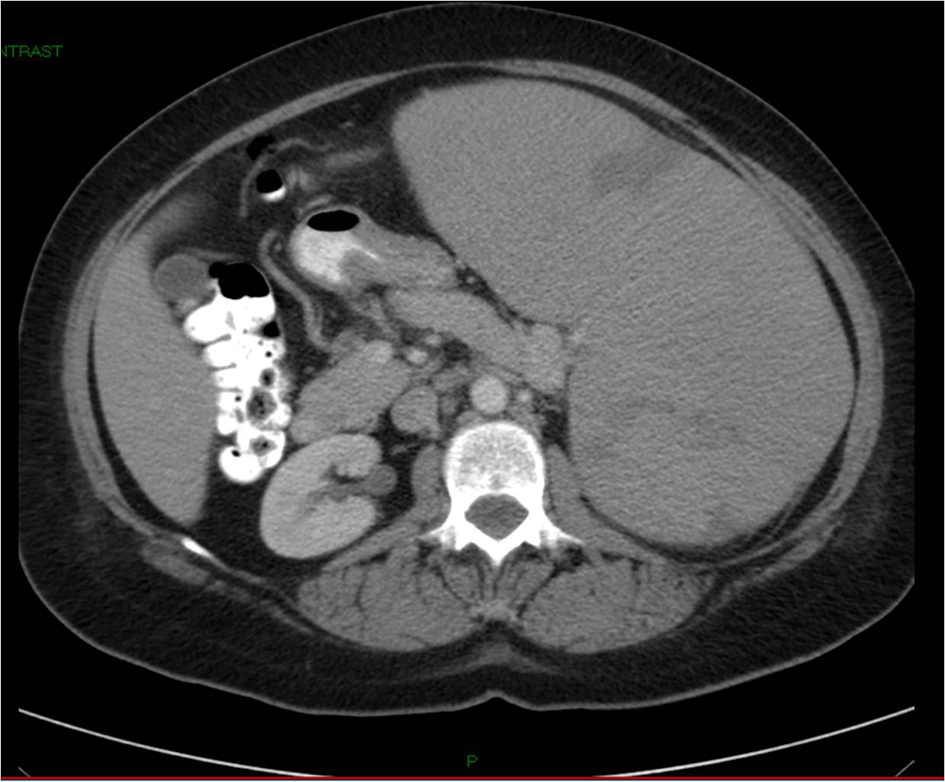

Лимфома яичка диагностика - фото презентация